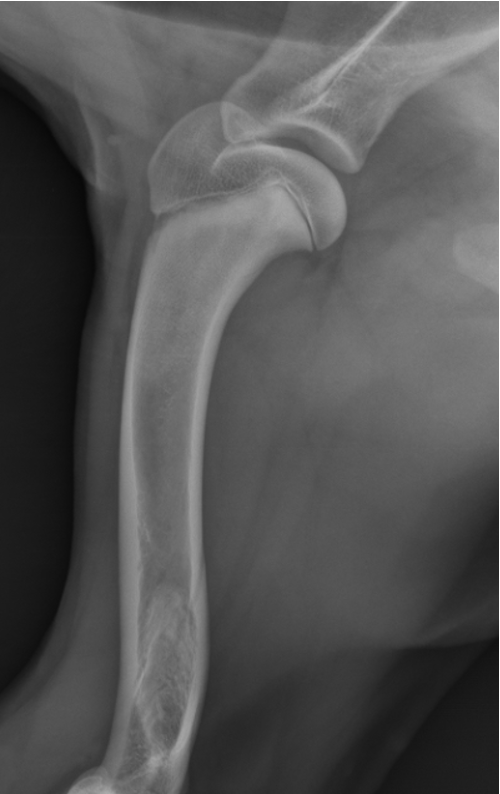

premature distal ulnar physis closure roentgen signs

gap - ulna and humerus, and gap at the bottom of ulna and carpus

cranial bowing of radius

premature distal radius physis closure roentgen signs

gap - radius and humerus, radius and carpus

no real ALD

which physis closed early

ulna

radius